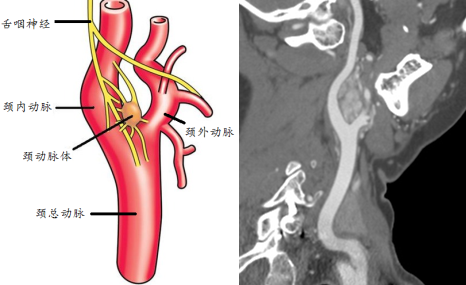

图2 颈动脉体位于颈动脉分叉,发生肿瘤则包绕血管。